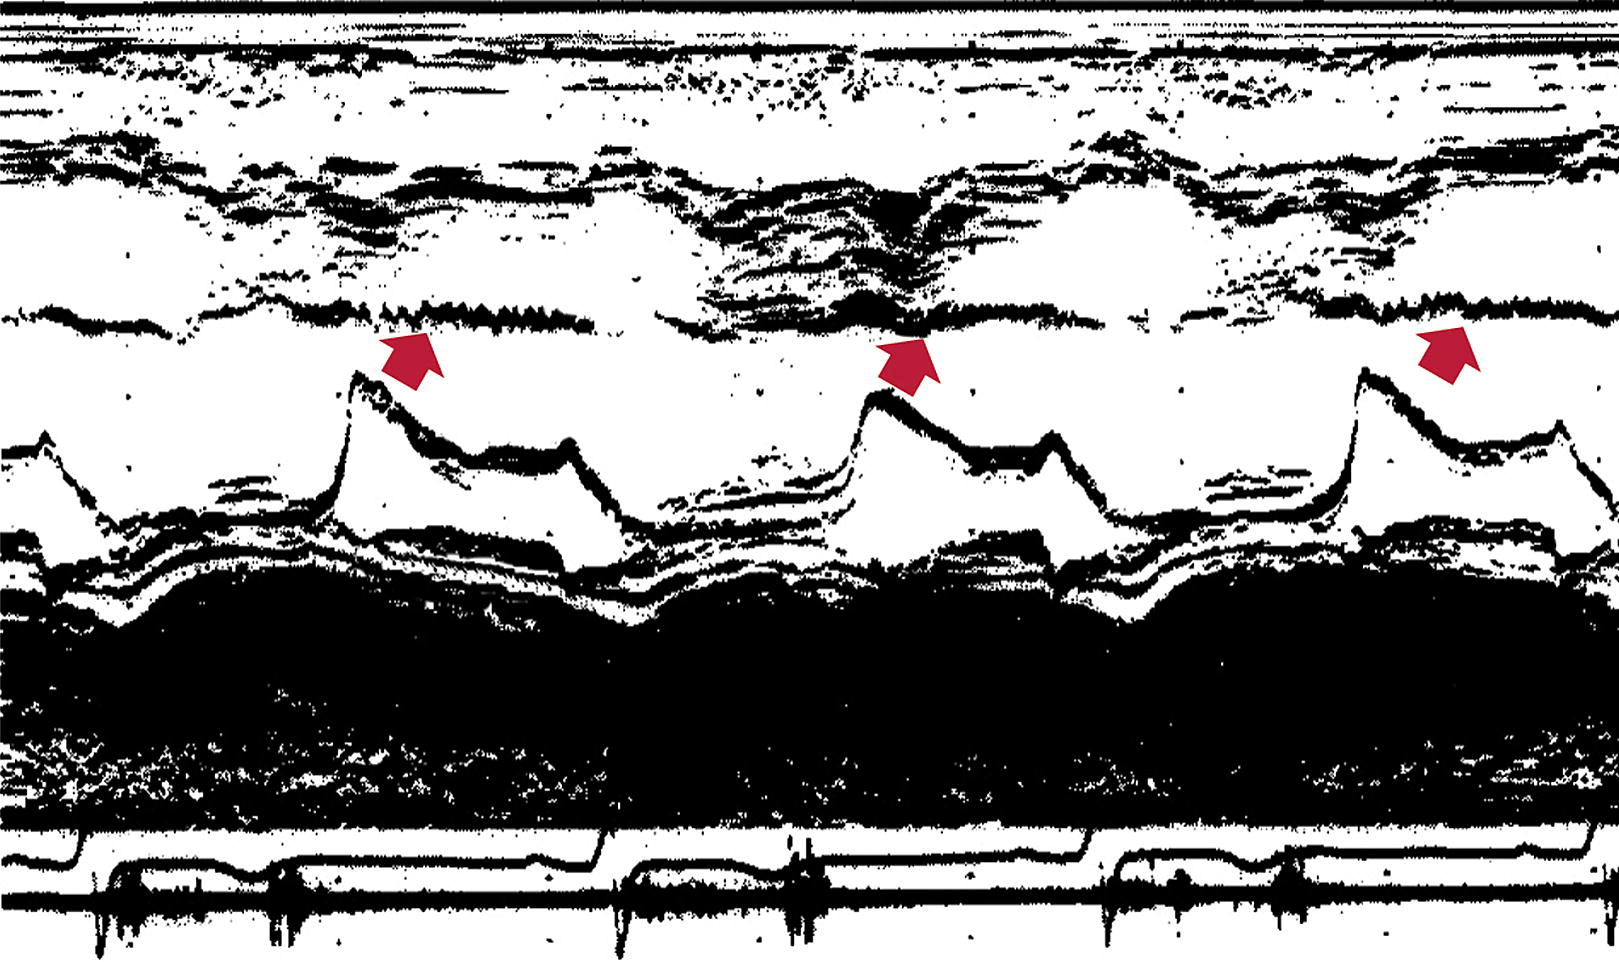

Fabrys

• Binary Sign: "hyperechogenic endocardial surface adjacent to a relatively hypoechogenic subendocardial layer"

• Concentric thickness is most common phenotype

• Asymmetric septal hypertrophy, eccentric hypertrophy, and apical hypertrophy also possible

• HCM cohorts, up to 12% diagnosed as Fabrys

• Should be on differential for HCM or unexplained hypertrophy

• Abnormalities in the atria, valves, aorta, and papillary muscles can also be seen